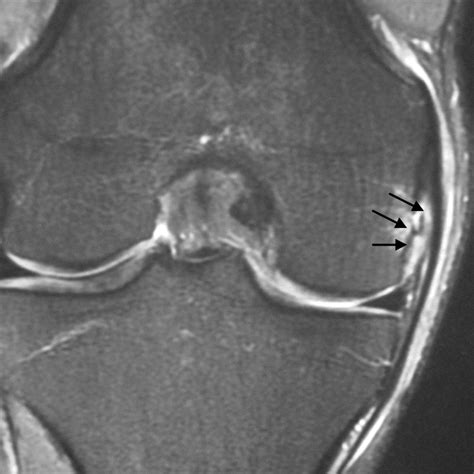

Diagnosing MCL Injuries

Diagnosing an MCL sprain vs. tear typically involves a combination of physical examination and imaging tests. A healthcare provider will assess the knee's stability, range of motion, and any areas of tenderness. Imaging tests, such as X-rays, MRI, or ultrasound, may be used to confirm the diagnosis and determine the extent of the injury.